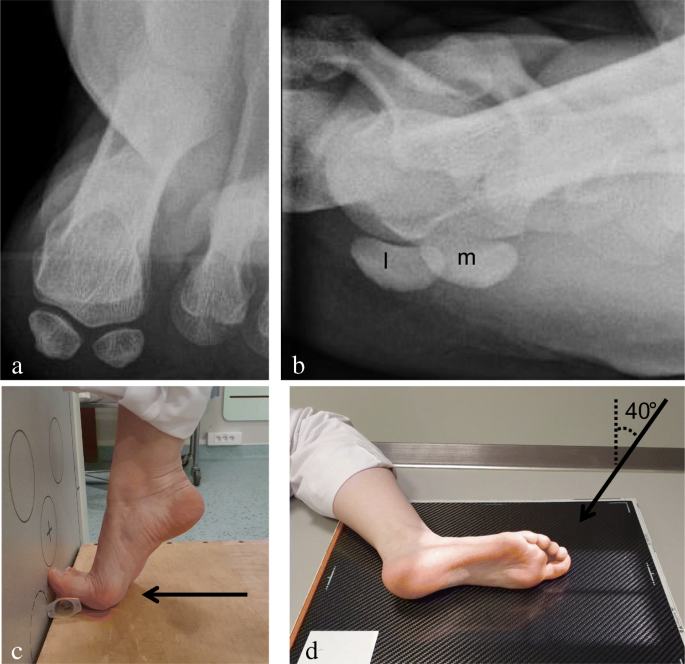

Sesamoid Bone X Ray Collection 2022 Sesamoid Bone X Ray Collection 2022

Sesamoid Bone X Ray

Sesamoid fracture | Radiology Reference Article | Radiopaedia.org Radiology Review - Sesamoid fracture | Axis Sports Med Toes (sesamoid view) | Radiology Reference Article | Radiopaedia.org Sesamoid | Radiology Reference Article | Radiopaedia.org Sesamoid bone - Wikipedia Sesamoid Bone X Ray